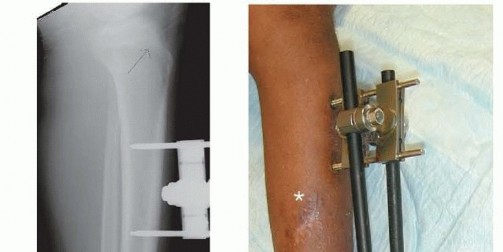

1. ## Plate Fixation

Treatment is essentially the same as for adult injuries, but several points bear emphasis.

It is helpful to make the incision slightly laterally over the anterior compartment so it will not lie directly over a medially placed plate (

TECH FIG 2A

).

The fracture is reduced using standard techniques. Care should be taken to avoid unnecessary stripping of the fracture.

I prefer to make an incision over the fracture large enough to reduce the fragments but not the entire length of the plate.

The plate can be slid under the skin, over the periosteum, and the screws placed through stab incisions, as for percutaneous plating in adults (

TECH FIG 2B

For larger children, many adult fracture systems include precontoured 3.5-mm plates for the distal tibia.

For smaller children, a small fragment plate may be contoured to fit appropriately.

It is important to avoid injury to the perichondral ring at the distal extent of the plate.

If the plate is applied on the medial side of the tibia, as it often is for fractures with valgus angulation, it will usually need to be removed after healing due to prominence.

If applied laterally, I usually make a longer incision because percutaneously placed screws will traverse the anterior compartment and potentially injure the neurovascular bundle. I prefer open placement in this case.

The wound is closed using standard techniques. A posterior splint is applied to protect the soft tissues.

TECH FIG 2 • A. Incision for open reduction and internal fixation is made laterally over the anterior compartment, and the skin can then be mobilized to gain access to the fracture site. It is important not to incise the skin directly over the proposed location of the plate. B. Medial view of internally fixed tibia. A lag screw compresses the fragment, and the plate stops short of the physis. The skin incision is centered over the fracture to allow an accurate reduction, but the proximal and distal screws can be placed percutaneously through a medially applied plate. It is helpful to make one stab incision for every two holes, centered between them.